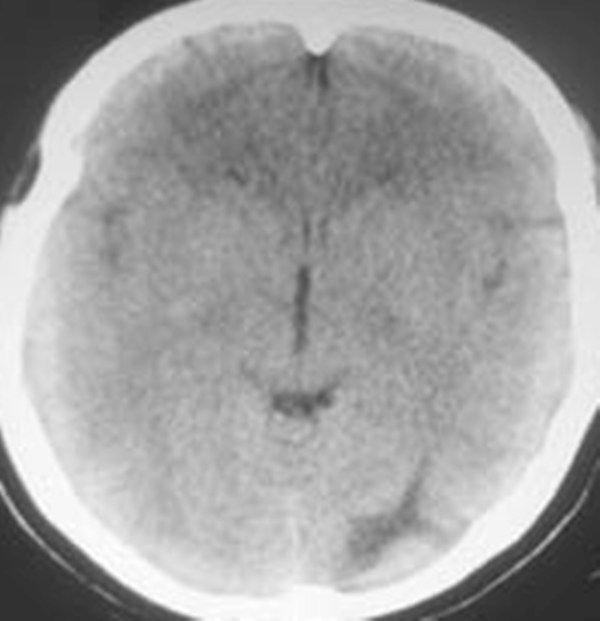

女。44岁,语言障碍三天,右侧上肢时而麻木。时而好转。其它图像未见异常。图像有点差请大家见谅。mg]/upload/forum/2009/02/0214453656449.jpg[/img]

蛛网膜囊肿

双侧额叶密度低,考虑线束老化或脑梗塞?

左侧枕叶脑软化灶?

双侧额叶脑梗塞,左侧枕叶脑软化灶,

临近脑沟五增宽,考虑蛛网膜囊肿